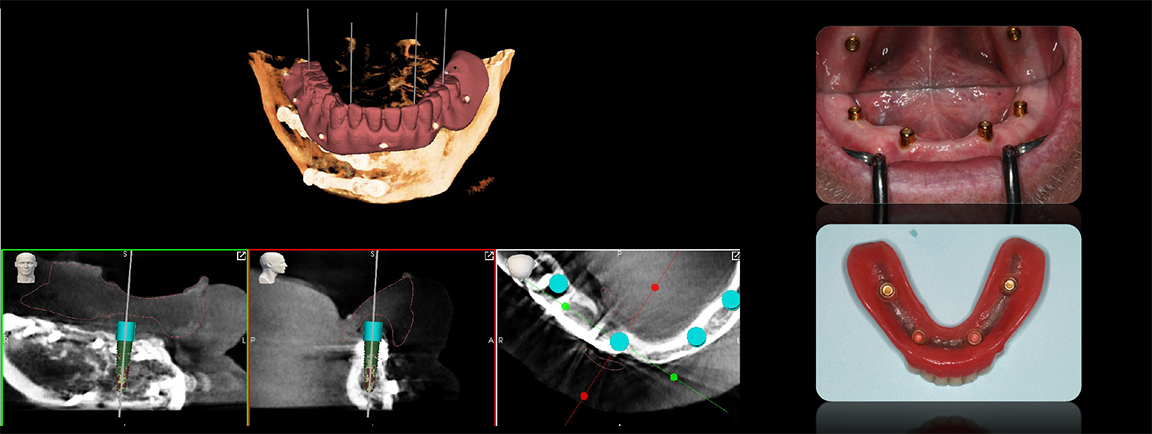

In such a patient, there may be little or no dental topography or teeth with which to work. The CT scan shows only the bony structure, which is what the practitioner is concerned with regarding dental implants, but from a treatment plan standpoint, the practitioner needs to visualize the way through and unwind the complex layers of such a puzzle. Robotics allow the practitioner to employ software on the front end and optimized for the robotic surgical approach in the middle, making the back-end treatment much easier. Scanning templates allow alignment of intraoral scans; the practitioner can add that result with high fidelity back to a CT scan that may otherwise have been unusable (Figure 9). The practitioner also can add other layers, including facial images to start building an improved version of the patient smile. With the data put into the robotic system, the plan is validated with easier to use digital versions that replace older analog treatment planning procedures involving alginate, stone models, articulators, and wax-ups.1-4

With robotics, whether for a simple one-implant procedure or a complicated overdenture or fixed attachable restoration procedure, the steps are the same, starting with aligning data in the robotic software from a treatment plan standpoint. In a case lacking trustworthy teeth, for example, the practitioner can align separate STL files relative to a patient x-ray (Figure 10) and have a blueprint on the screen so that, when designing the implants foundation for yet-to-be-achieved teeth, he or she knows that they will line up.3,4

Fig 9. Scanning templates allow alignment of intraoral scans.

Figure 9

Fig 10. The practitioner can align separate stereolithographic files relative to a patient x-ray.

Figure 10